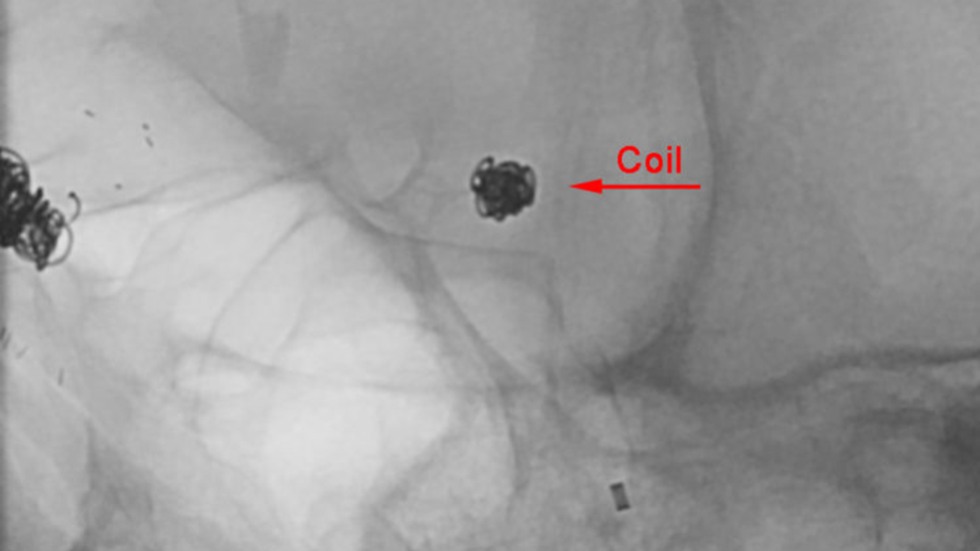

Endovascular Repair

Endovascular (from within the blood vessel) surgery, is performed through a catheter (a hollow, flexible tube) delivered from the groin or leg to the blood vessels in the brain. Thin platinum wires are pushed into the aneurysm, where they conform to the wall of the aneurysm forming a coil mass. Since blood clots form around the coils, the chances of a rupture are greatly reduced. Recovery time is typically only one to three days.

Technique: Coil

2 of 3

Technique: Treated Aneurysm

3 of 3